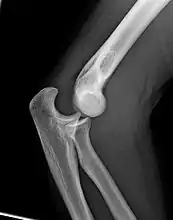

Joint

The elbow joint has three different portions surrounded by a common joint capsule. These are joints between the three bones of the elbow, the humerus of the upper arm, and the radius and the ulna of the forearm.

When in anatomical position there are four main bony landmarks of the elbow. At the lower part of the humerus are the medial and lateral epicondyles, on the side closest to the body (medial) and on the side away from the body (lateral) surfaces. The third landmark is the olecranon found at the head of the ulna. These lie on a horizontal line called the Hueter line. When the elbow is flexed, they form a triangle called the Hueter triangle, which resembles an equilateral triangle.[5]

At the surface of the humerus where it faces the joint is the trochlea. In most people, the groove running across the trochlea is vertical on the anterior side but it spirals off on the posterior side. This results in the forearm being aligned to the upper arm during flexion, but forming an angle to the upper arm during extension — an angle known as the carrying angle.[6]